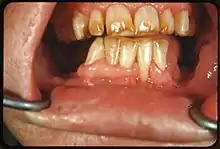

• Tobacco: Tar in smoke from tobacco products (and also smokeless tobacco products) tends to form a yellow-brown-black stain around the necks of the teeth above the gumline.[12]